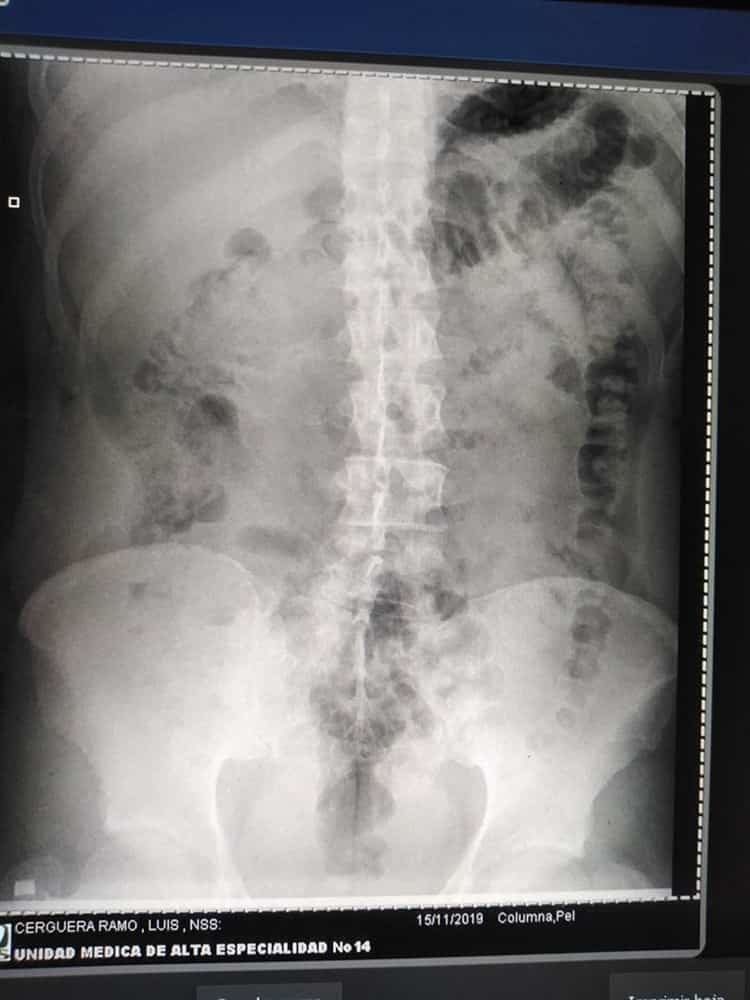

Además de los golpes externos que presentó por el accidente, radiografías muestran lesiones en la columna que requieren ser tratadas por un especialista para poder sanar.